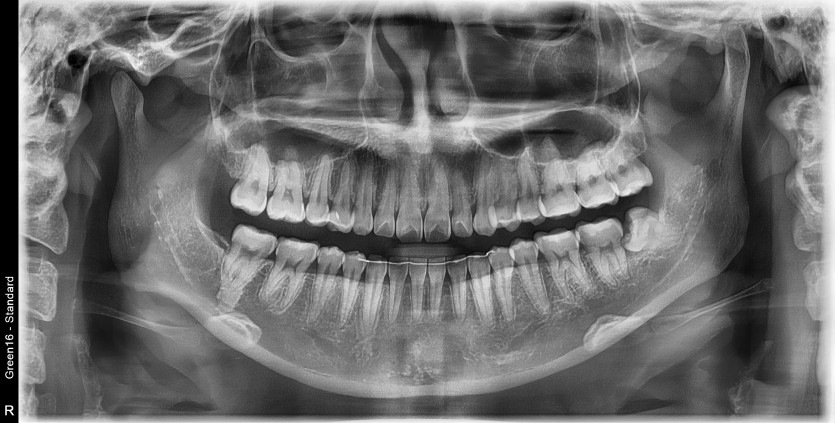

#38 사랑니 발치

구강 외과 전문의가 당일 발치했습니다.